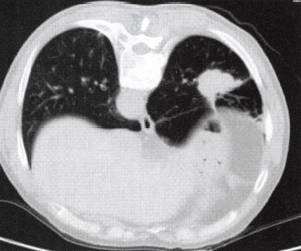

(1)周围型肺癌基本X线表现为肺内孤立的球形灶,不同组织类型的肺癌在大小、 医学百科网 | YxBaike.Com

密度、边缘形态及瘤体周围特点有一定差异。CT的优势在于可显示瘤体内密度、坏死、血供特点及临近结构浸润情况。除边缘凹凸不平,呈分叶征外,常可见边缘毛刺、瘤周血管集束征、胸膜凹陷征、内部空洞形成,多壁厚薄不均,内缘凹凸不平或见壁结节。无或少有气液平为其特征(图2)。增强检查病灶可见明显强化,CT值增加25Hu以上。高度提示 肺癌。 医学百科网 | YxBaike.Com